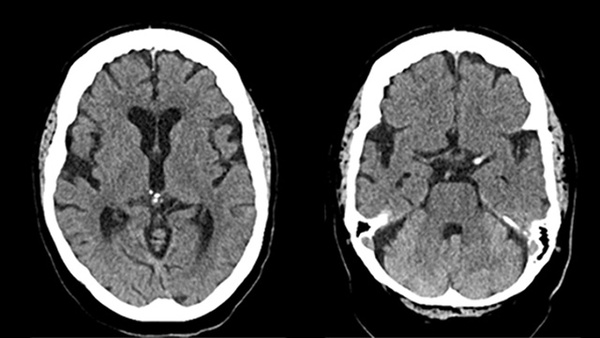

On November 21, the landmark CREST-2 trial was published in the prestigious New England Journal of Medicine . This two-arm study evaluated whether adding carotid artery stenting or carotid endarterectomy to optimal medical therapy provides additional benefit in patients with ≥70% carotid stenosis and no prior cerebrovascular events.

Carotid artery stenting combined with medical therapy reduced the risk of ischemic events at 4-year follow-up compared with medical therapy alone.